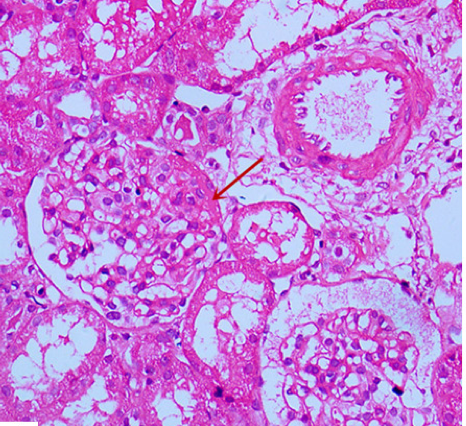

Based on the written consent of the child’s guardian, the child underwent renal biopsy.

In our case, the renal biopsy was suggestive of mild-to-moderate MsPGN. Good prognosis to treatment with both steroids and MMF was reported.